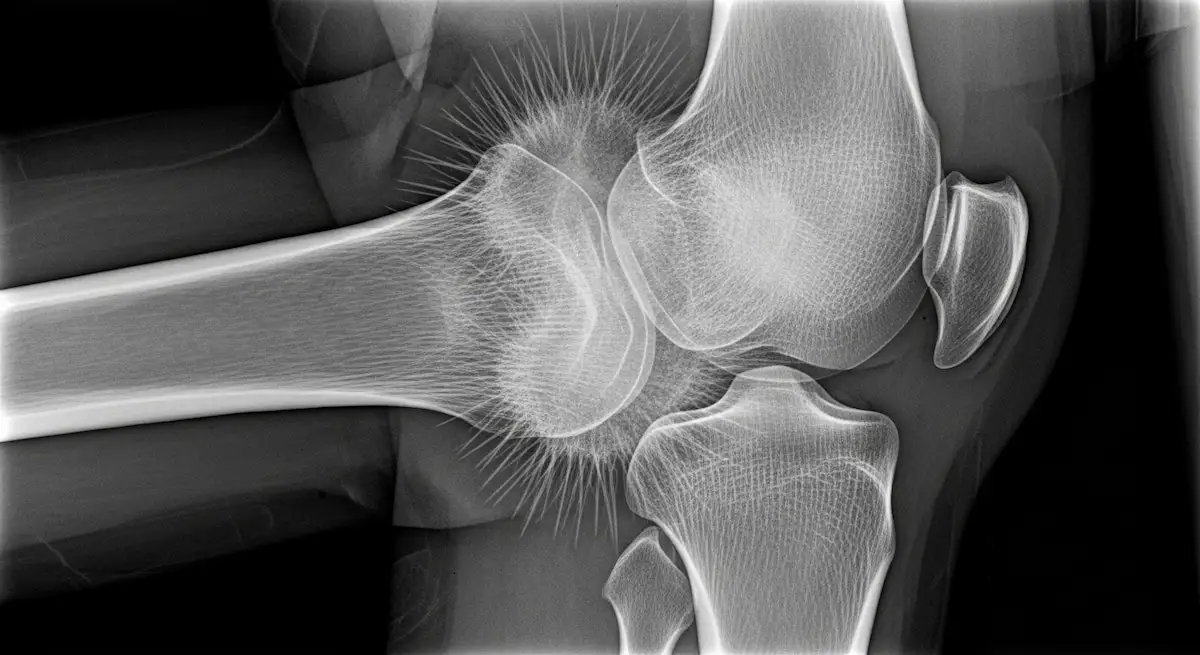

O osteossarcoma do joelho é um câncer ósseo agressivo que costuma aparecer perto da placa de crescimento, nas extremidades do fêmur ou da tíbia.

O osteossarcoma nasce de osteoblastos, que são as células que produzem osso. No joelho, aparece com maior frequência nas pontas do fêmur (distal) e na parte alta da tíbia (proximal).

O primeiro passo é a radiografia do joelho, que muitas vezes já mostra alterações típicas.